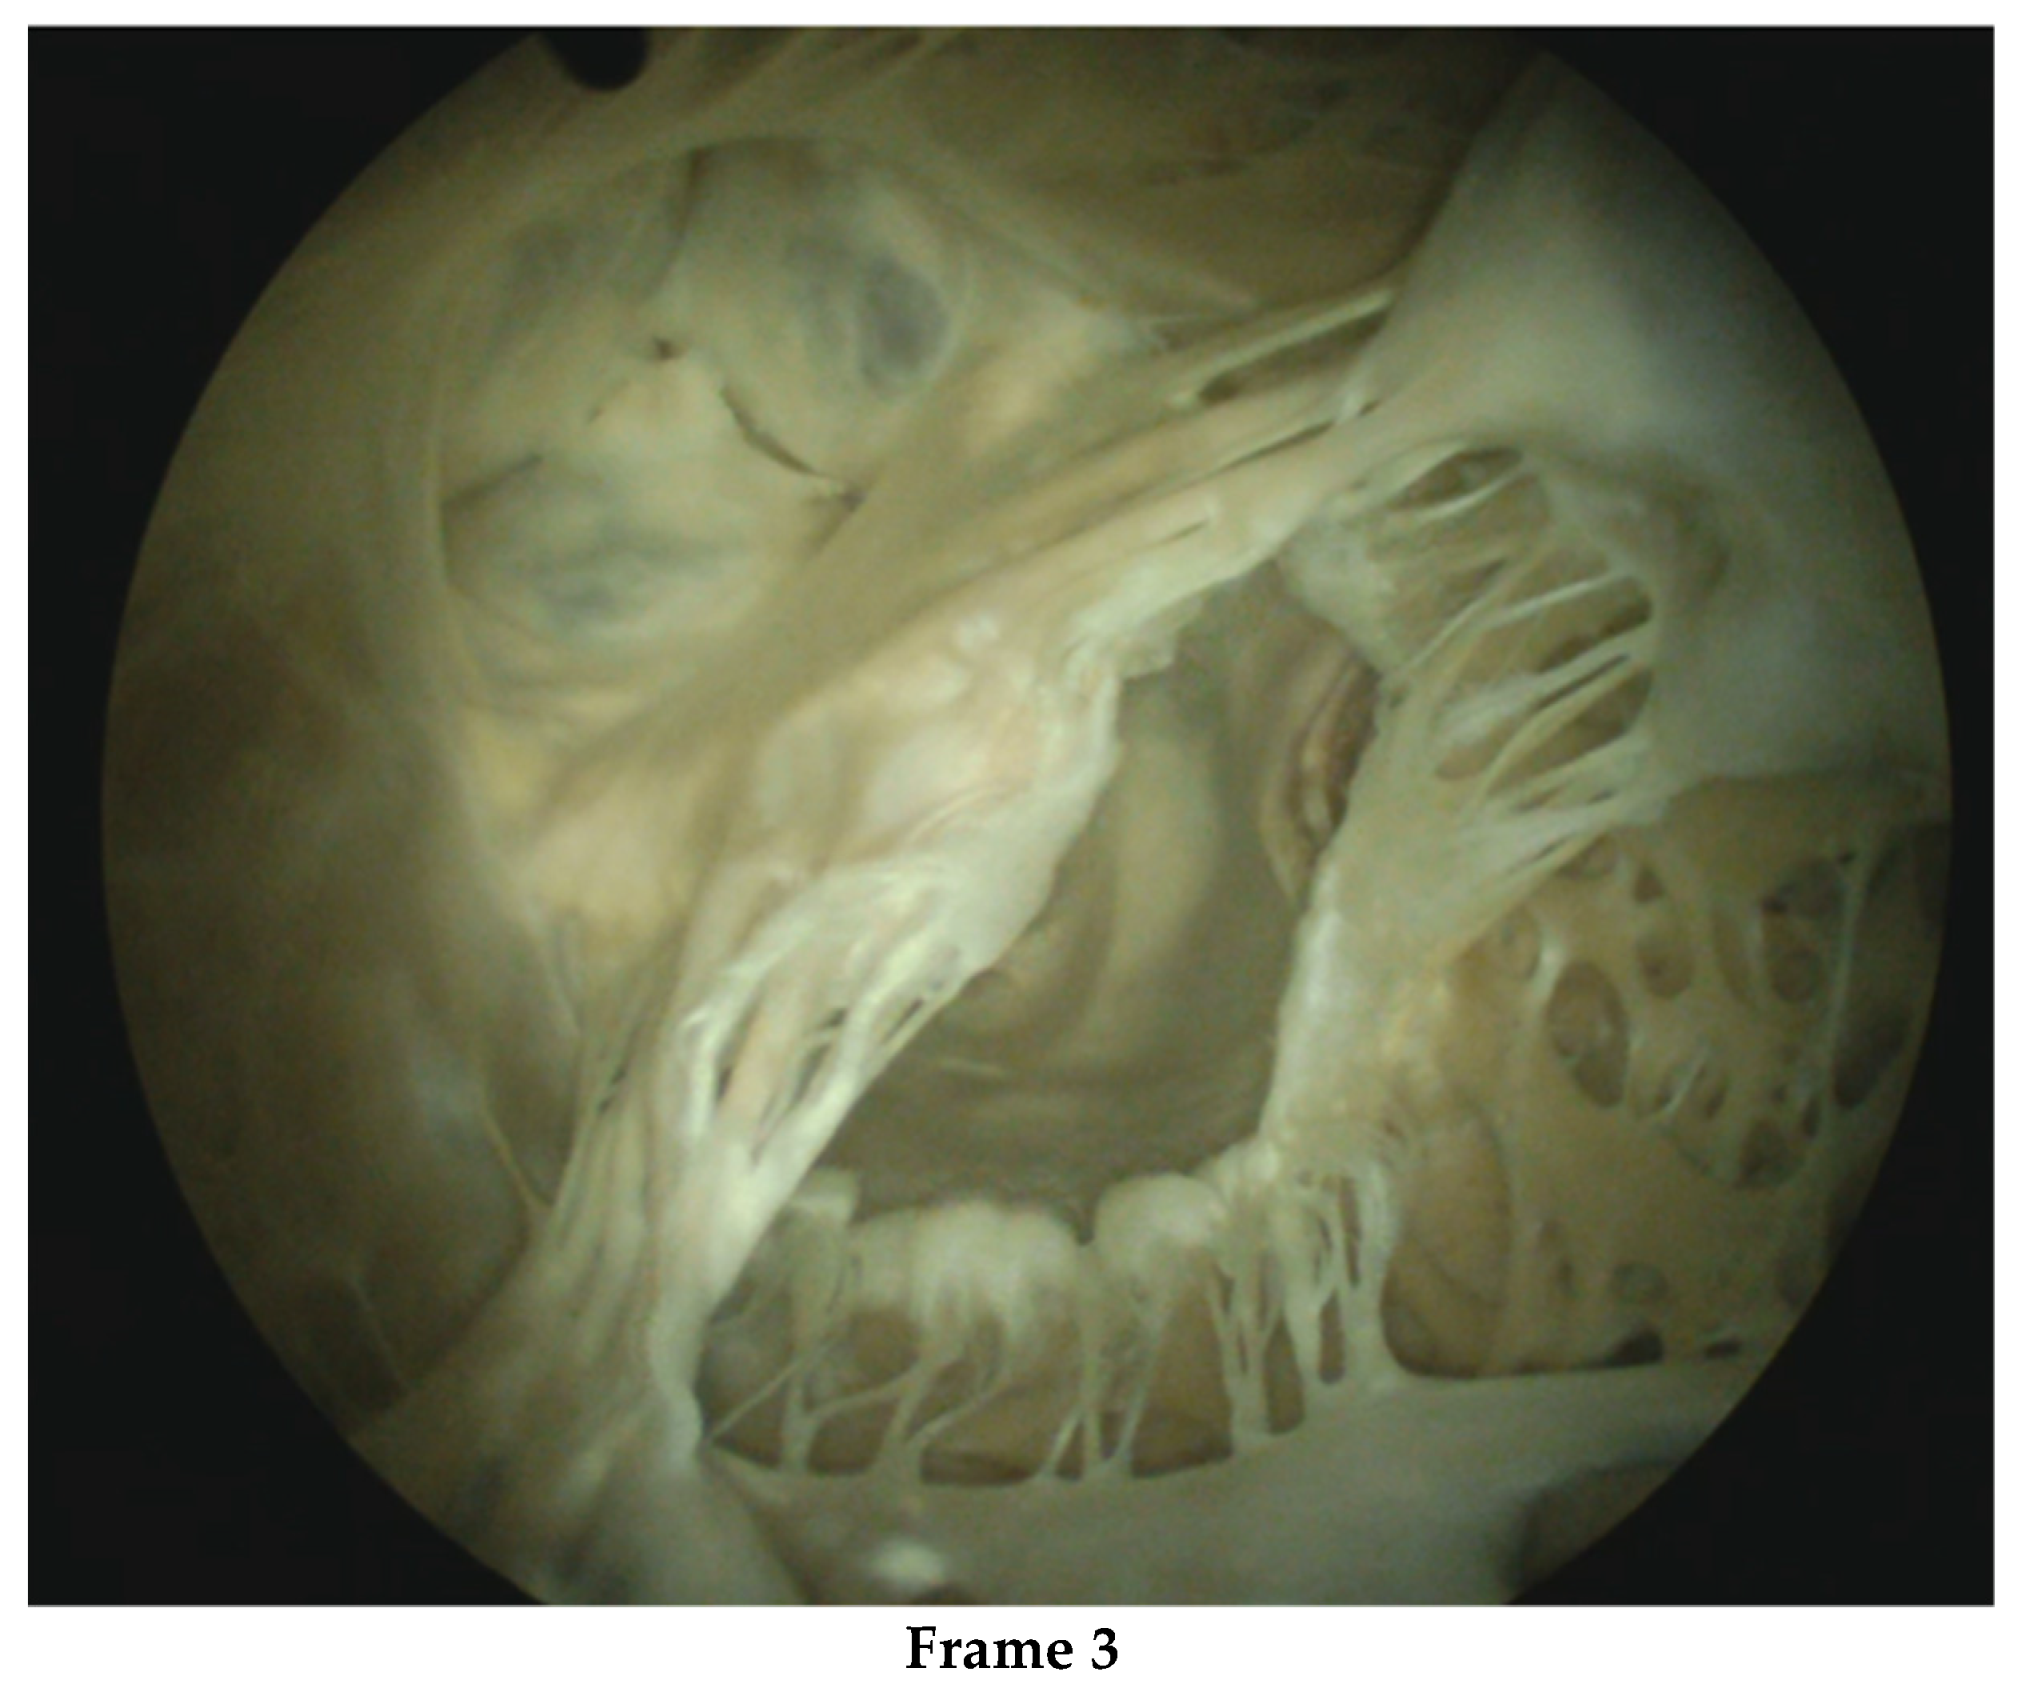

- Nia, P.S.; Heuts, S.; Daemen, J.; Luyten, P.; Vainer, J.; Hoorntje, J.; Cheriex, E.; Maessen, J. Preoperative planning with three-dimensional reconstruction of patient’s anatomy, rapid prototyping and simulation for endoscopic mitral valve repair. Interact. Cardiovasc. Thorac. Surg. 2017, 24, 163–168. [Google Scholar] [CrossRef]

- Daemen, J.H.T.; Heuts, S.; Olsthoorn, J.R.; Maessen, J.G.; Nia, P.S. Mitral valve modelling and three-dimensional printing for planning and simulation of mitral valve repair. Eur. J. Cardio-Thorac. Surg. 2019, 55, 543–551. [Google Scholar] [CrossRef] [PubMed]

- Makhdom, F.; Hage, A.; Manian, U.; Ginty, O.; Losenno, K.L.; Kiaii, B.; Chu, M.W. Echocardiographic Method to Determine the Length of Neochordae Reconstruction for Mitral Repair. Ann. Thorac. Surg. 2021, 111, 519–528. [Google Scholar] [CrossRef]

- Nia, P.S.; Daemen, J.H.; Maessen, J.G. Development of a high-fidelity minimally invasive mitral valve surgery simulator. J. Thorac. Cardiovasc. Surg. 2019, 157, 1567–1574. [Google Scholar] [CrossRef]